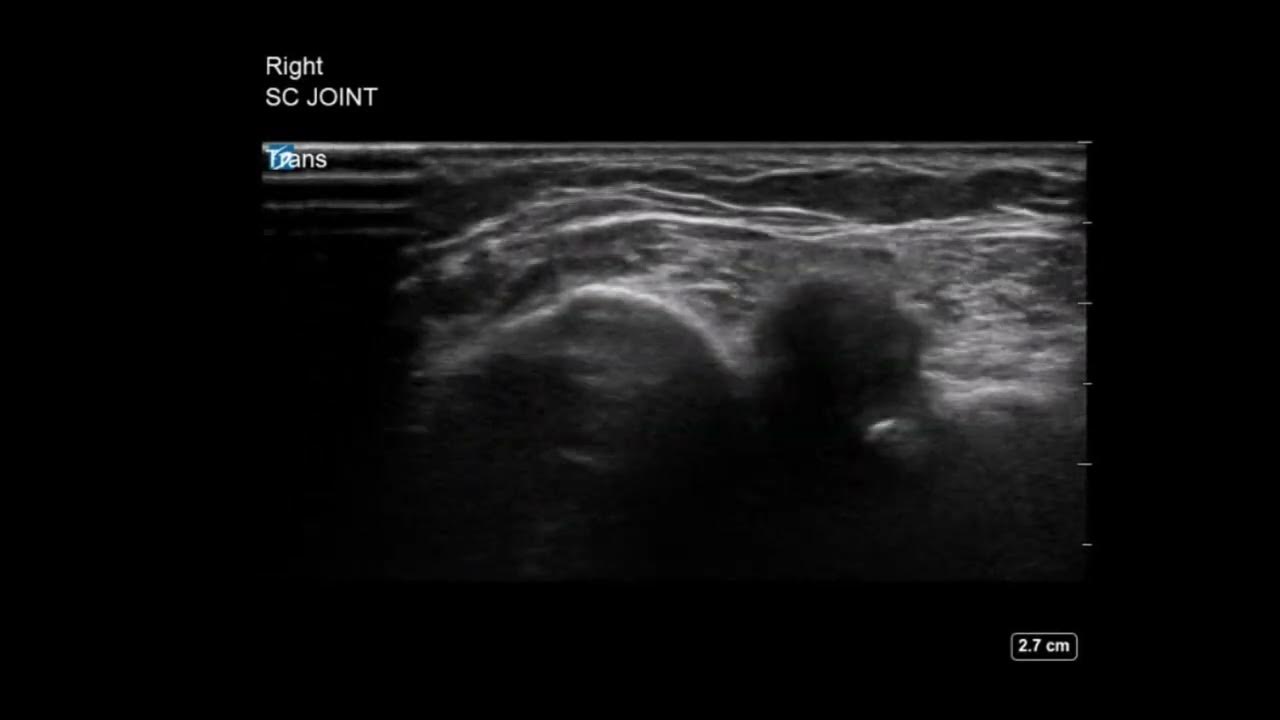

Sternoclavicular Joint Ultrasound Sternoclavicular Joint Calcification Radiology A pdf document that reviews the normal anatomy and common abnormalities of the sternum and sternoclavicular joints, with imaging examples and discussion. Computed tomography (ct) scanning was done the next day, and revealed soft‐tissue swelling and calcification anterior to the right. The sternoclavicular radiographic series is a used to evaluate sternoclavicular joint and the proximal clavicle. The sternum and sternoclavicular. Sternoclavicular Joint Calcification Radiology.

Shoulder Ultrasound Sternoclavicular Joint Osteoarthritis YouTube Sternoclavicular Joint Calcification Radiology A pdf document that reviews the normal anatomy and common abnormalities of the sternum and sternoclavicular joints, with imaging examples and discussion. The sternoclavicular radiographic series is a used to evaluate sternoclavicular joint and the proximal clavicle. Learn about the anatomy, sonographic technique, and spectrum of findings of the sternoclavicular joint (sclj), a synovial joint that connects the sternum and. Sternoclavicular Joint Calcification Radiology.

Ultrasound of the left sternoclavicular joint showing a fluid Sternoclavicular Joint Calcification Radiology Learn about the anatomy, sonographic technique, and spectrum of findings of the sternoclavicular joint (sclj), a synovial joint that connects the sternum and the clavicle. Learn about the sternoclavicular joint, a synovial joint between the medial clavicle, manubrium and the first costal cartilage. A pdf document that reviews the normal anatomy and common abnormalities of the sternum and sternoclavicular joints,. Sternoclavicular Joint Calcification Radiology.